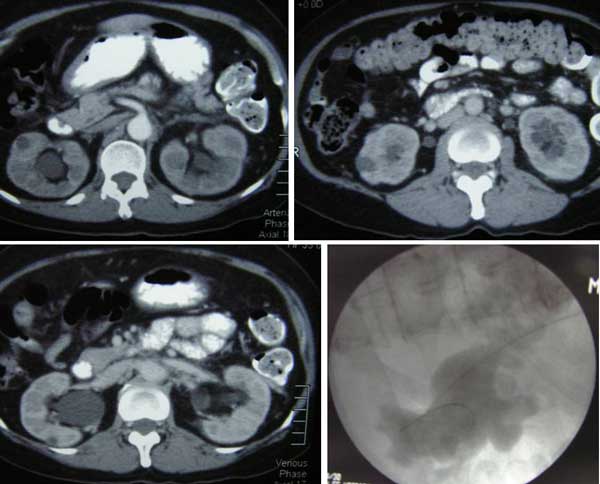

CT report dated 27 April 2012 indicated: Multiple simple renal cortical cysts seen bilaterally. Moderate right hydronephrosis and hydroureter as well as mild left hydronephrosis and hydroureter seen. Grossly distended urinary bladder. Fuzzy, irregular cervical edges noted. Impression: 1. Grossly distended urinary bladder with bilateral urinary tracts ? back pressure. 2. Fuzzy, irregular cervical edges. Suggest gynaecological assessment.